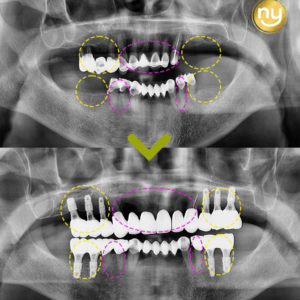

울산안아픈치과 신경치료 후 염증 치아재식술로 해결해요! 안녕하세요. 울산안아픈치과 뉴욕연합치과입니다. 임플란트가 워낙 보편화되고 선호하는 분들이 많아지고 있지만, 자연치아를 살리고자 하는 수요도 급상승하고 있는 추세입니다. 위 환자분은 충치가 많이 진행되어 신경치료한 치아를 사용하고 있었습니다. 하지만, 오랜 기간이 지나 치아 뿌리 끝에 염증이 생겨 발치를 권유받았는데요, 발치를 하더라도 치아 뿌리만 손상 더보기…